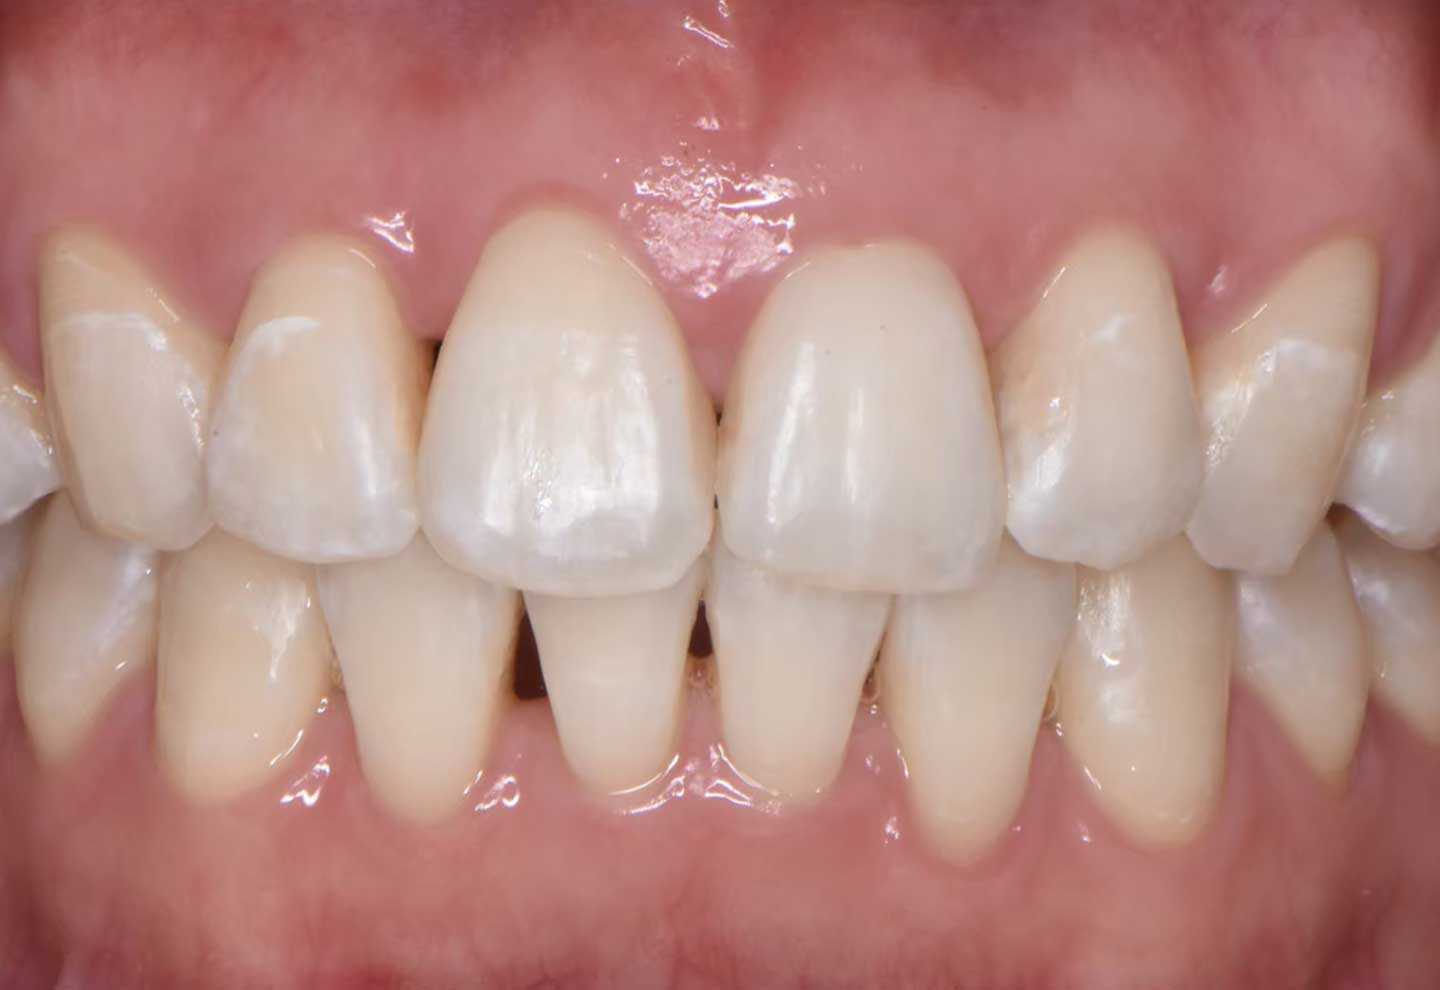

オールジルコニア(人工ダイヤモンド)症例

| 治療内容 |

セラミック治療 |

| 治療期間 |

約2か月 |

| 費用 |

約36万円(セラミック3本分) |

| リスク・副作用 |

セラミックは欠ける可能性がある |